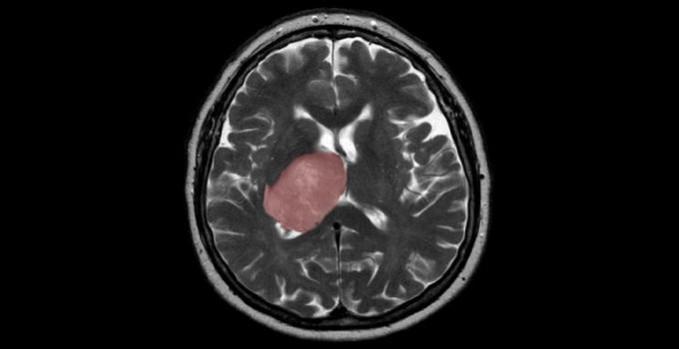

The cancer-causing virus Epstein Barr Virus (EBV) can infect the neuronal cells and drive various changes in biomolecules such as fatty acids, carbohydrates, and protein components, leading to diseases of the central nervous system as well as brain cancer, scientists have found.

The study, published in the journal ACS Chemical Neuroscience, showed that there could be timely and gradual changes in various biomolecules in the neuronal cells under viral influence. Additionally, these changes were distinct when compared to the changes observed in other supportive brain cells (that is, astrocyte and microglia).

They observed that the lipid, cholesterol, proline, and glucose molecules increased in the cells under viral influence, and these biomolecular entities could ultimately play pivotal roles in the viral usurpation of cells.